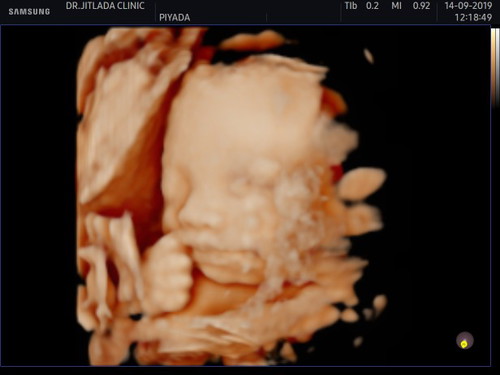

4 มิติ 26+3 กว่าจะหันหน้ามาให้เห็นอิแม่ต้องลุกกินน้ำเย็น3รอบ

ชัดดีจังเลยคะ